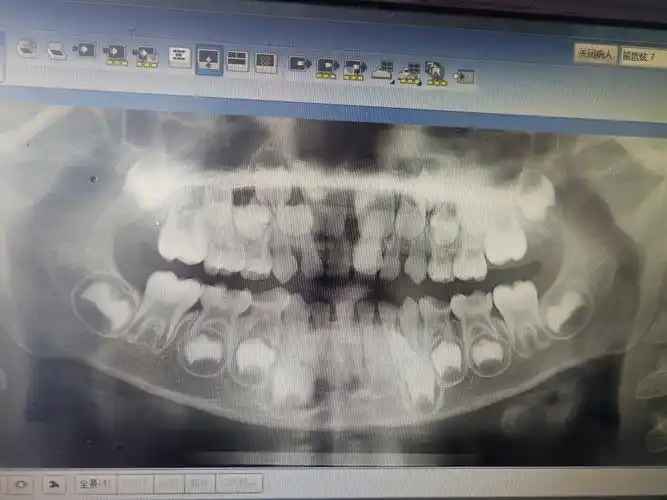

孩子今年7岁,这是在诊所拍的片子,哪位内行人能帮忙看看这个上中切牙